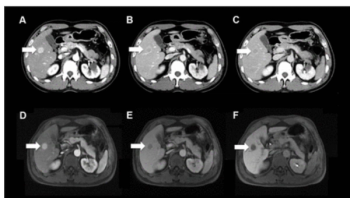

LI-RADS category 5 (LR-5) assessment had an 11 percent higher AUC for detecting hepatocellular carcinoma (HCC) in patients with non-cirrhotic chronic hepatitis C (CHC) in comparison to those with cirrhotic CHC.